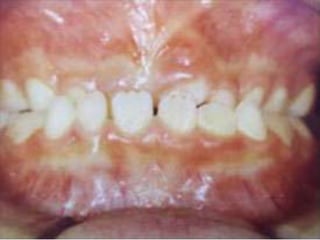

ANTERIOR CROSSBITE

A malocclusion in which one or more of the upper

anterior teeth occlude lingually to the mandibular

incisors; the lingual malpositions of one or more

maxillary anterior teeth in relation to the

mandibular anterior teeth when the teeth are in

centric relation occlusion

This is when the upper incisors are in reverse overjet and occlude lingual to the

lower incisor. An example of this would be an extreme class III incisor relationship.

ANTERIOR CROSSBITE A malocclusionin which one or more of the upper anterior teeth occlude lingually to the mandibular incisors; the lingual malpositions of one or more maxillary anterior teeth in relation to the mandibular anterior teeth when the teeth are in centric relation occlusion

This is whenthe upper incisors are in reverse overjet and occlude lingual to the lower incisor. An example of this would be an extreme class III incisor relationship.